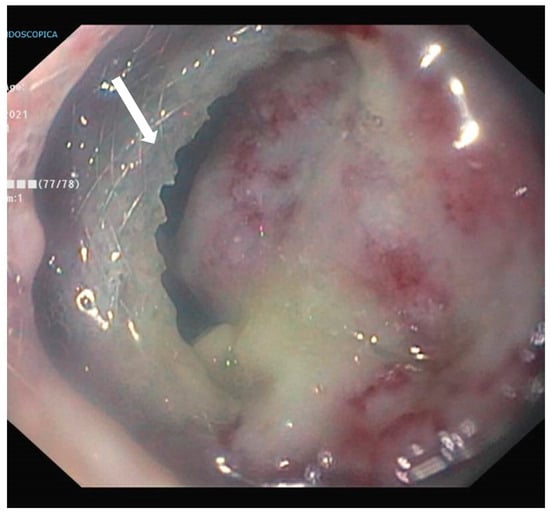

4. Case Presentation